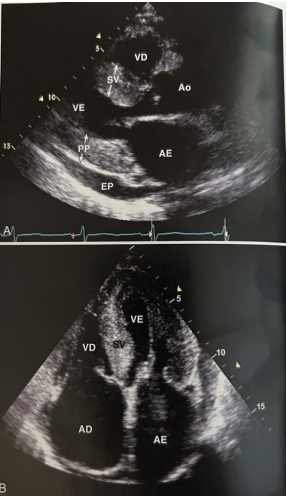

Ecocardiograma transtorácico com as seguintes imagens:

Braunwald – Tratado de Doenças Cardiovasculares – 9ª Ed. Cap. 15. Figura 15-78.

Baseado no caso clínico descrito, o diagnóstico mais provável é